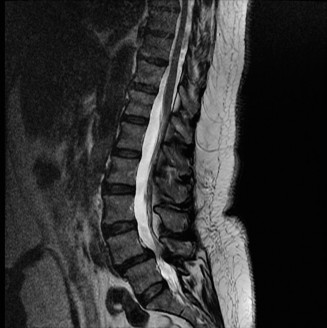

To contextualize the decision-making algorithm, consider the classic presentation of a middle-aged patient with multiple medical comorbidities. A paradigmatic case involves a 48-year-old obese female (Body Mass Index of 43) with poorly controlled diabetes mellitus who presents with severe, unrelenting low back pain, fevers, and chills. Advanced imaging, specifically magnetic resonance imaging (MRI), typically demonstrates discitis involving the L4–5 disc space with adjacent osteomyelitis of the L4 and L5 vertebral bodies. Crucially, in many early or medically responsive cases, there is an absence of epidural abscess formation, and standing radiographs reveal relatively normal sagittal and coronal alignment. When such a patient is neurologically intact—lacking saddle anesthesia, bowel/bladder incontinence, or upper motor neuron signs—the immediate clinical imperative shifts from urgent surgical decompression to aggressive pathogen identification and targeted antimicrobial therapy.

When surgical intervention becomes unavoidable, meticulous pre-operative planning is the cornerstone of a successful outcome. Advanced imaging is non-negotiable. An MRI with and without gadolinium contrast is the gold standard for defining the extent of the epidural abscess, the degree of neural compression, and the involvement of adjacent paraspinal musculature (e.g., psoas abscess). T1-weighted images typically show hypointense signals in the infected marrow, while T2-weighted and STIR sequences reveal hyperintense fluid and edema in the disc space and vertebral bodies. Gadolinium enhancement highlights the vascularized inflammatory phlegmon and the capsule of any abscesses.